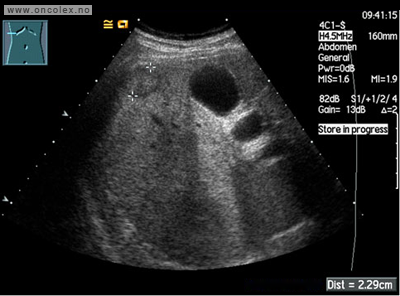

CT  med kontrast er den mest brukte røntgenundersøkelsen. Kontrastvæsken gis gjennom en kanyle (venflon) i armen. Svulster i leveren synes oftest best på MR. MR eller CT-tynntarm kan påvise nevroendokrine svulster i tynntarmen som ikke ses på vanlig MR/CT.

Bildeeksempler